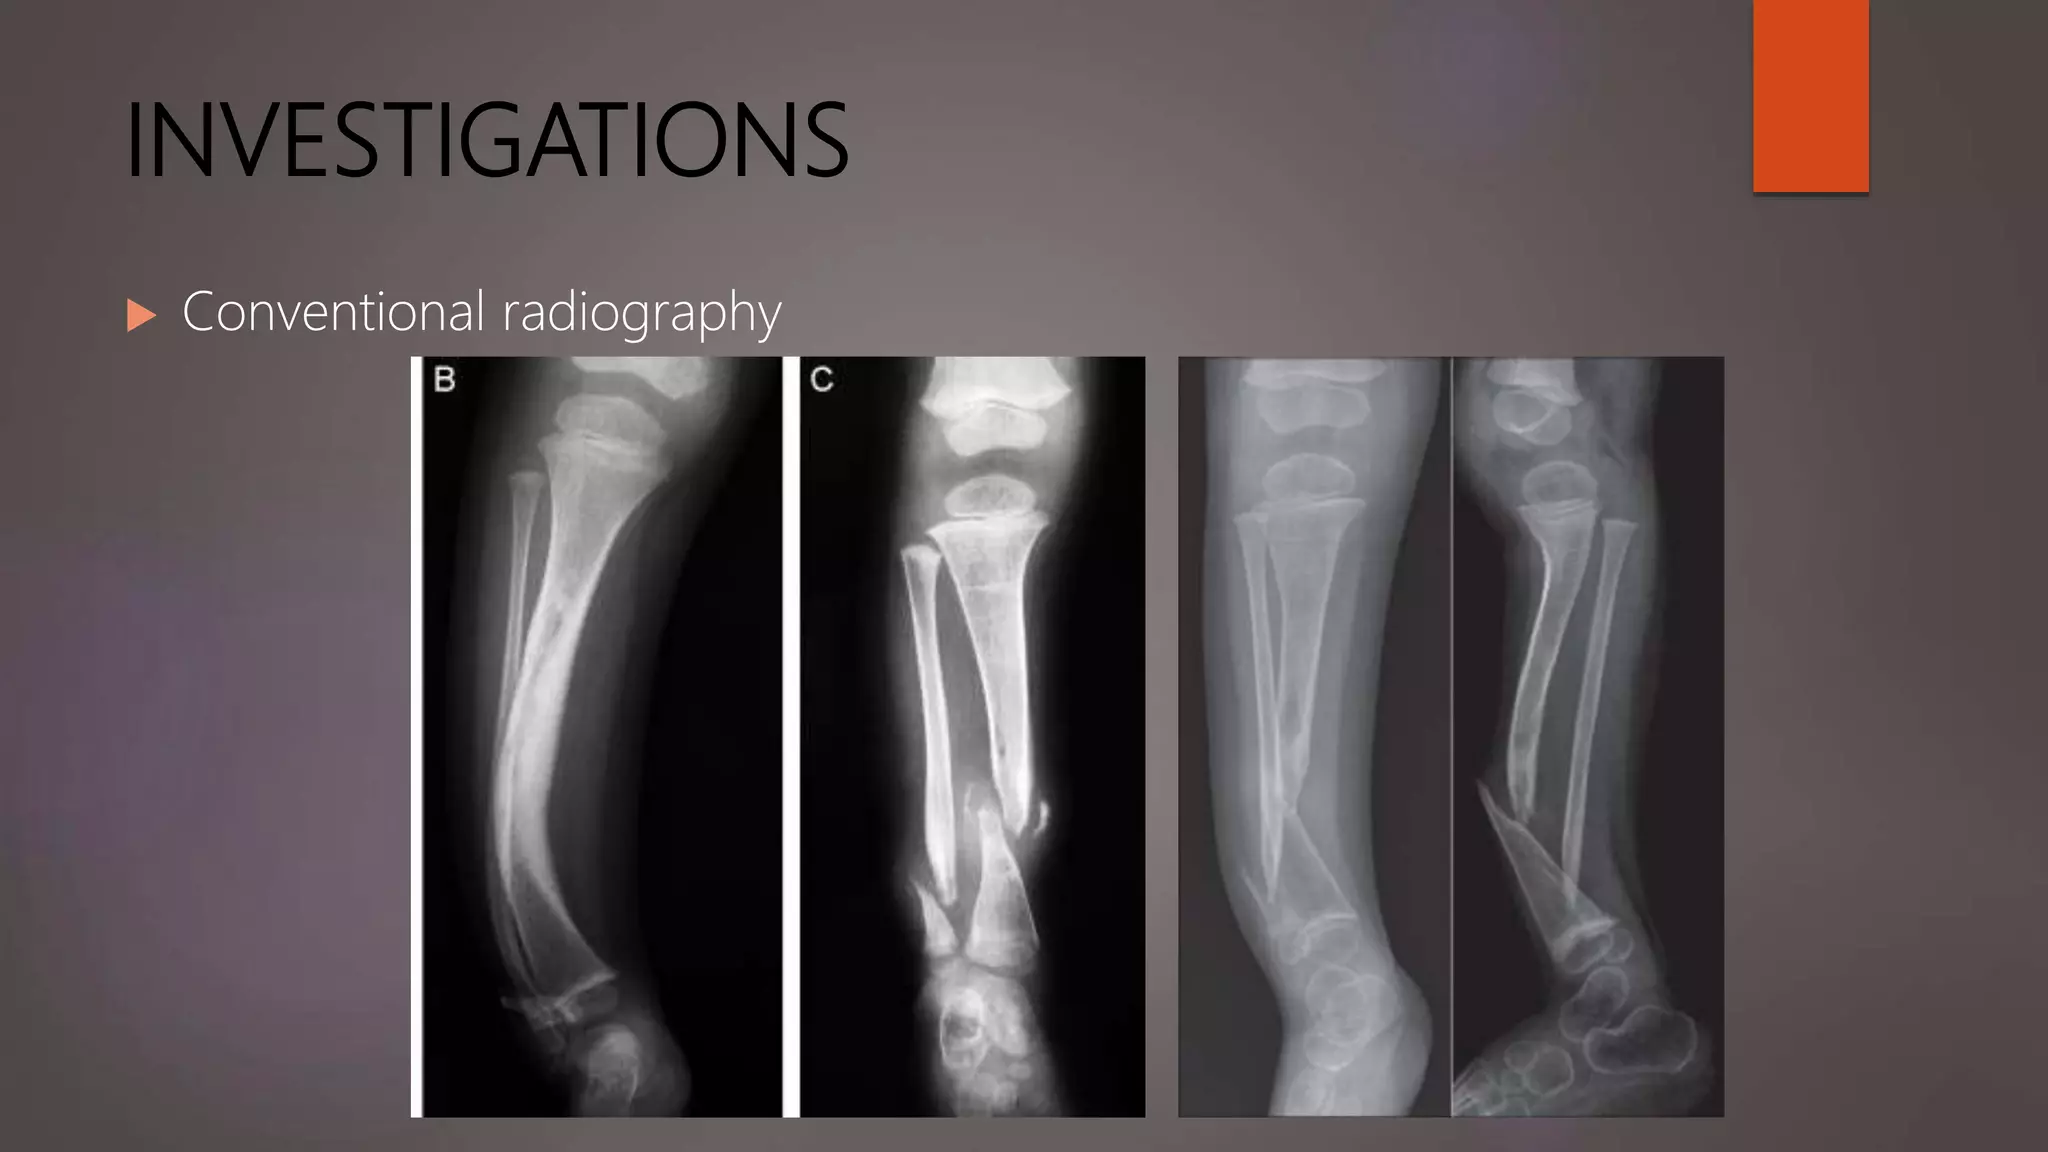

INVESTIGATIONS

 Conventional radiography